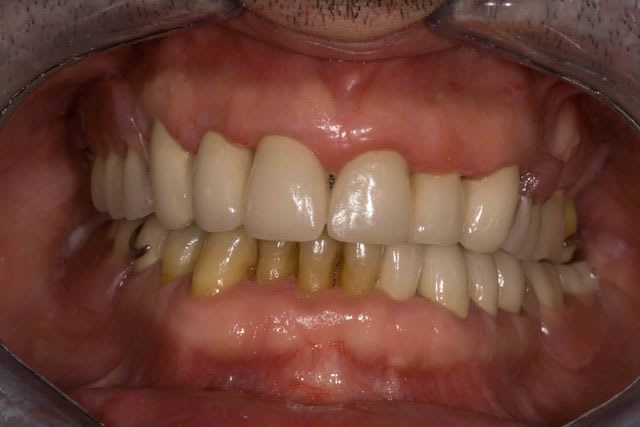

Mais la, apres 1 an de traitements reguliers, entre les lambeaux d'assainissements, les élongations coronaires et les reprises de traitements pourrave j'ai enfin BOUCLE CE CAS !

A l'origine le patient ne voulait surtout pas touché aux dents encore " saine" car il les trouvait bien.

Maintenant il les trouve jaunes et veux les blanchir. Comme quoi un nouveau sourire amene souvent un nouveau regard.